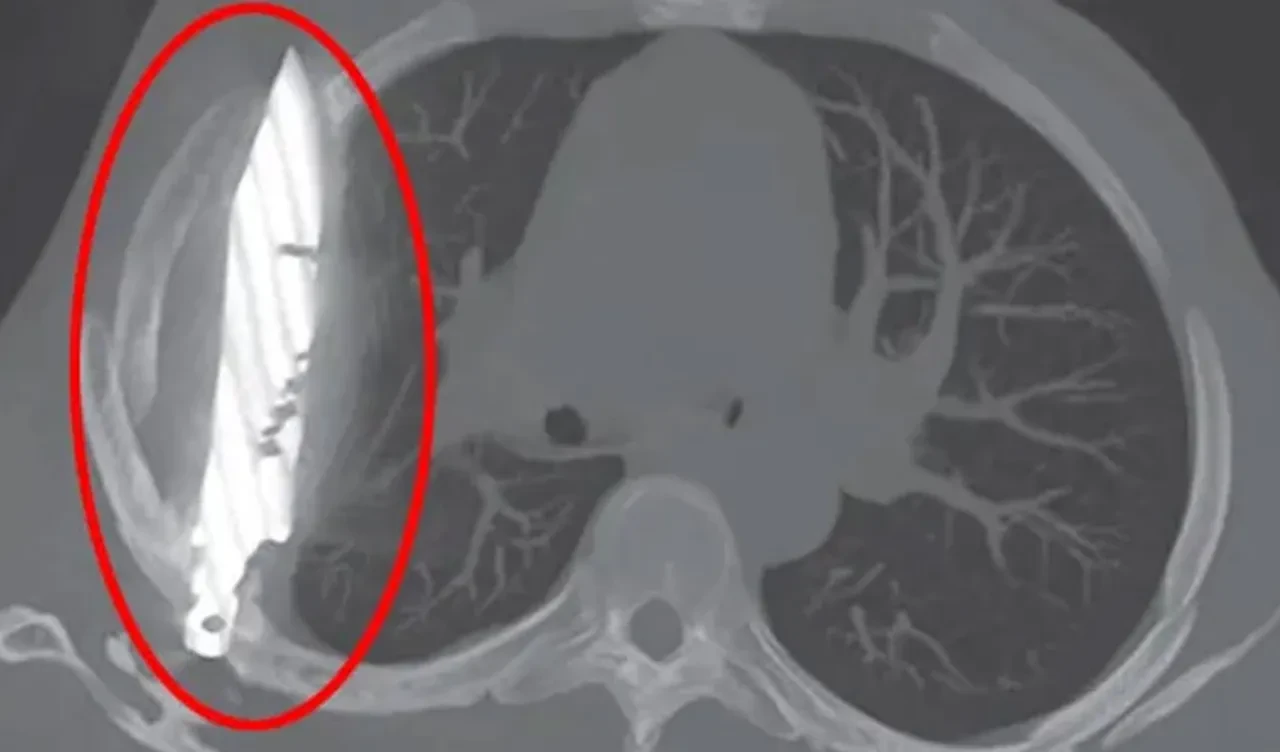

Doktorlar, röntgen çekilmesini istedi ve ardından büyük bir şok yaşandı. Adamın göğsünde bir bıçak olduğu ortaya çıktı. Hasta, seneler önce bir kavga esnasında, sırtından, göğsünden ve karnından yaralandığını, tedavi gördüğünü söyledi. O zamandan bu zamana kadar ise herhangi bir sağlık sorunu yaşamadığını söyledi.

Doktorlar, tedavi sırasında bıçağın unutulmuş olabileceğini, iltihap yapmasıyla beraber ortaya çıktığını ifade etti. The Sun'ın haberine göre, bıçak, sağ kürek kemiğinden girip hayati organlara zarar vermeden göğüste kaldı.

Hastanın 8 yıldır göğsünde taşıdığı bıçak, ameliyatla çıkarıldı ve ölü doku temizlendi. Hasta, sağlığına kavuştu.